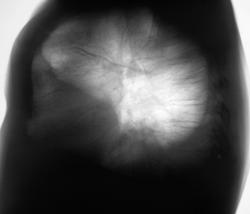

Правосторонний экссудативный плеврит с "затеканием" экссудата в главную междолевую щель. Плевра в междолевых щелях утолщена.

Правосторонний экссудативный плеврит.